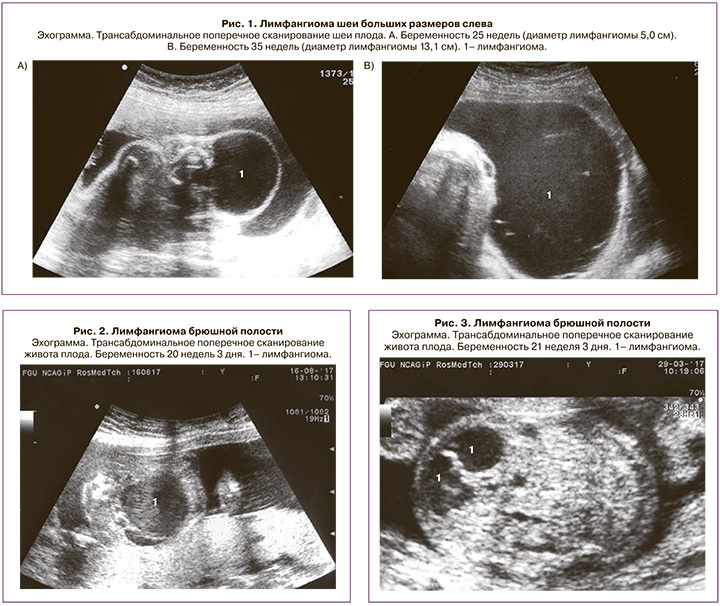

Как отмечено выше, лимфангиома шеи составила около половины всех наблюдений – 28 (51,8%). Из них в 2 (7,1%) наблюдениях образования распространялись также на подчелюстную область, в 3 (10,7%) – на голову, в 1 (3,6%) – в подмышечную область, в 3 (10,7%) – на грудную стенку и в 1 (3,6%) – в средостение. У 2 новорожденных лимфангиома шеи была гигантского размера и достигала в диаметре более 10 см (рис. 1). В одном из этих наблюдений у ребенка диагностирована также врожденная анемия вследствие пренатального массивного кровоизлияния в кистозные полости. Все новорожденные поступили в отделение хирургии новорожденных, где было проведено дополнительное обследование.

Под нашим наблюдением находились 6 пациентов с абдоминальной лимфангиомой (11,1%). Срок беременности на момент выявления варьировал от 20 до 37 недель. Из них в 4 наблюдениях произошли срочные роды, дети поступили в отделение хирургии новорожденных, где всем было проведено оперативное лечение с благоприятным исходом; при этом в одном из наблюдений лечение проведено лапароскопическим доступом. Прерывание беременности по медицинским показаниям проведено в сроке 20 недель беременности у одной пациентки (диаметр абдоминальной лимфангиомы составил 3,7 см; также у плода была диагностирована кистозная дисплазия левой почки) (рис. 2). В одном случае в сроке 25 недель произошло спонтанное исчезновение ранее выявляемого образования (в сроке 21 неделя диаметр составлял 2,4 см) (рис. 3).